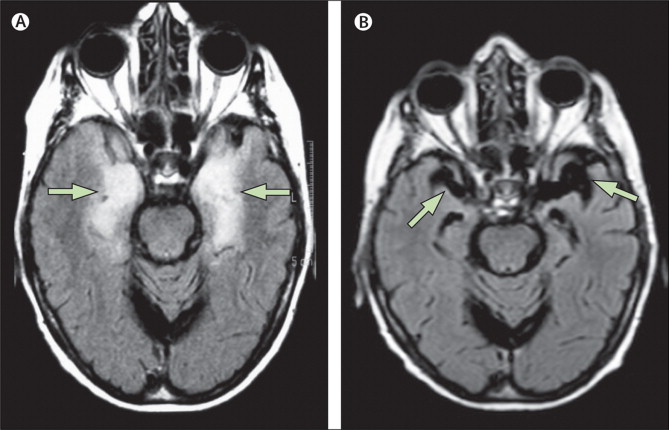

边缘叶脑炎(Limbic encephalitis,LE)

戚晓昆:重视边缘叶脑炎的诊断与鉴别_边缘叶脑